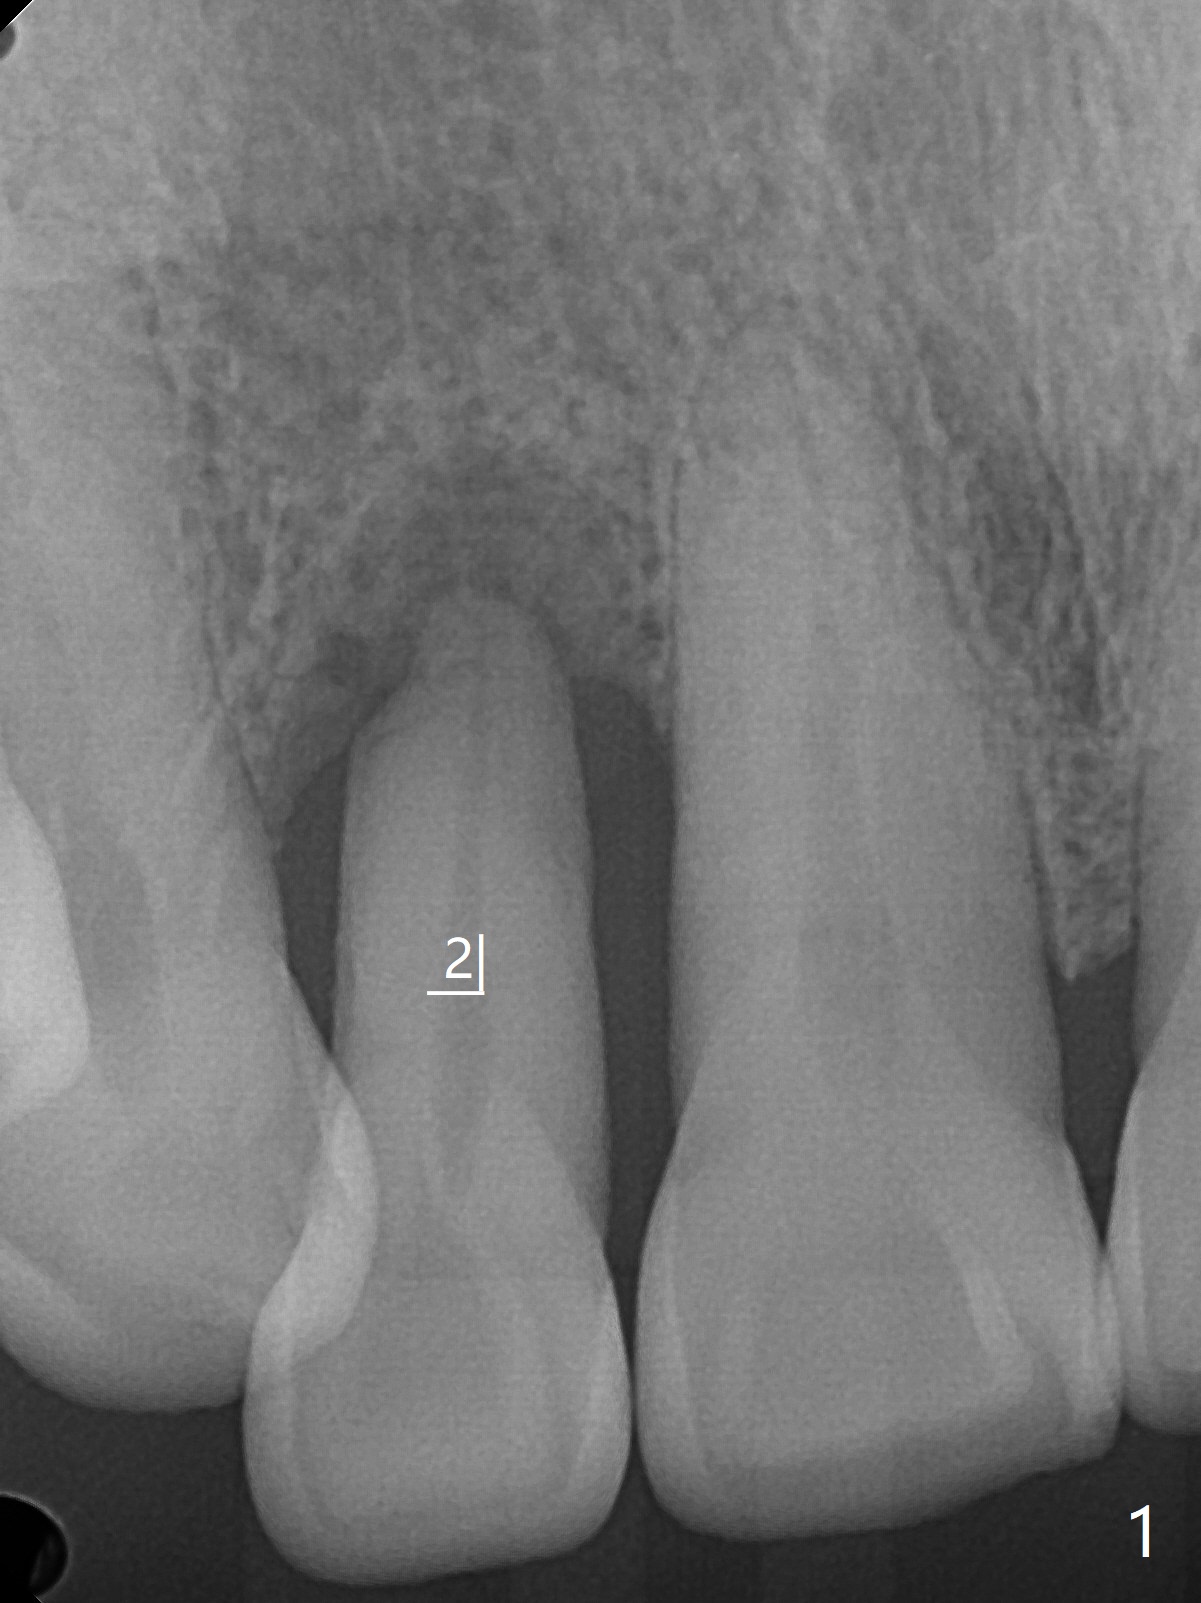

68岁男要求拔除右上2松动牙(图一),尽管近远中空间大,不能象左上2种大植体(图二,五)。右上2骨质吸收严重,植体应该植入深,牙龈厚(6毫米,图三,四),需要长基台,放置粘性骨粉修复骨质缺失。PRF膜好像用处不大,PRF上清液适当多用于制作粘性骨粉。准备牙周洁治器和Endogain,让骨粉与邻牙牙根结合。